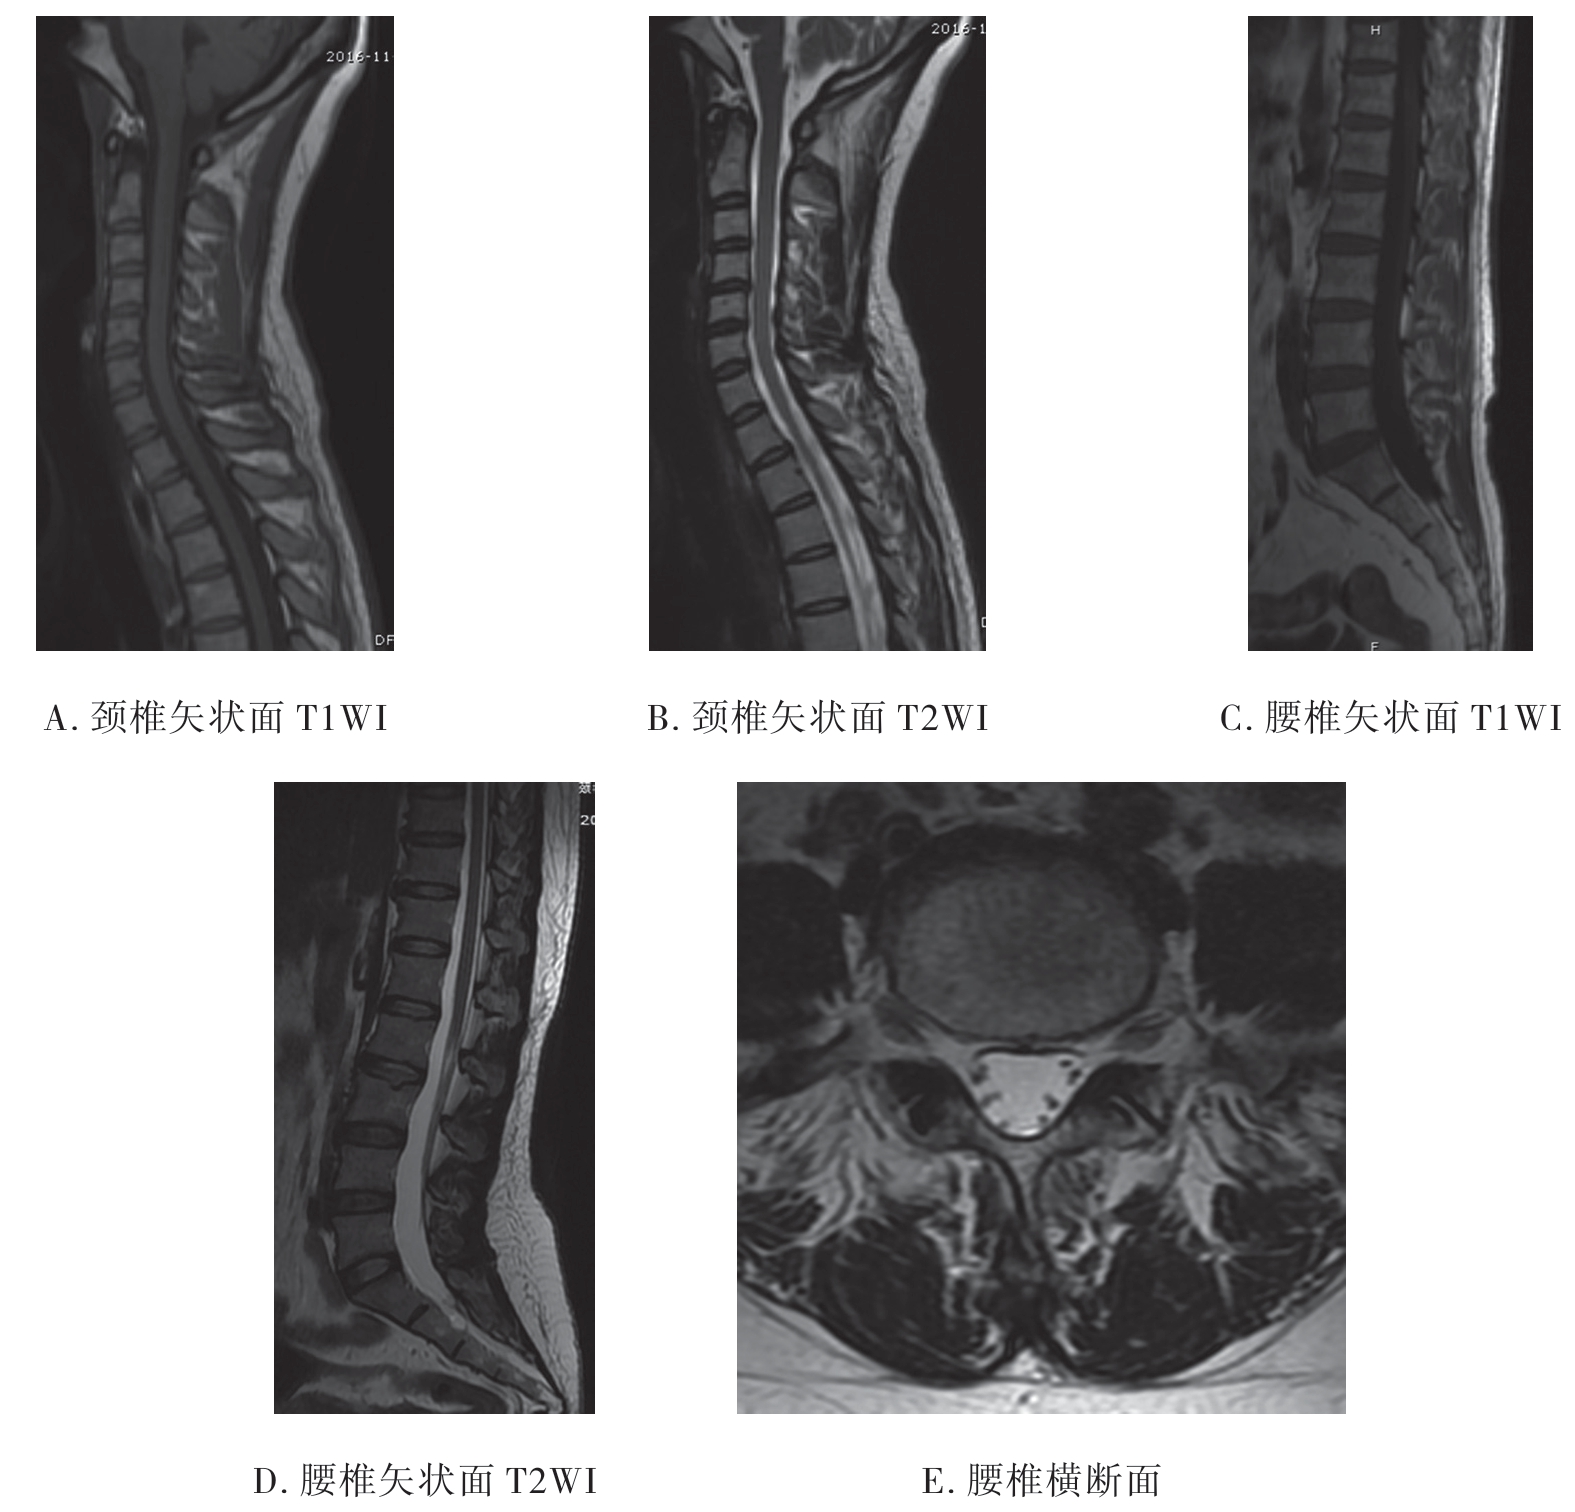

3.脊柱MRI影像 脊椎骨性结构的皮质骨及韧带在T1WI和T2WI上均表现为黑影的低信号;椎间盘在T1WI上不能区分纤维环和髓核,在T2WI上纤维环表现为黑影的低信号,而髓核则为白影的高信号;正中矢状面T1WI上脊髓呈带状灰影的中等信号,边缘光滑、信号均匀,位于椎管中心部位,其前后为低信号的脑脊液;T2WI上脊髓仍为中等信号,其前后的脑脊液呈白影的高信号。横断面上可清楚显示脊髓、脊神经及其与周围的关系(图7-2-8)。

图7-2-8 正常脊椎MRI影像

3.MRI检查 MRI能清楚显示脊髓及神经根损伤、韧带、椎间盘及软组织损伤等。损伤的椎体呈粉碎性破裂,椎管断裂、变形;矢状位椎体有不同程度移位,椎间盘破裂并移位,骨折脊椎成角畸形;急性期损伤的脊椎均伴有骨挫裂伤,相邻的脊髓受压变形(图7-2-16)。

图7-2-16 MRI示爆裂性骨折